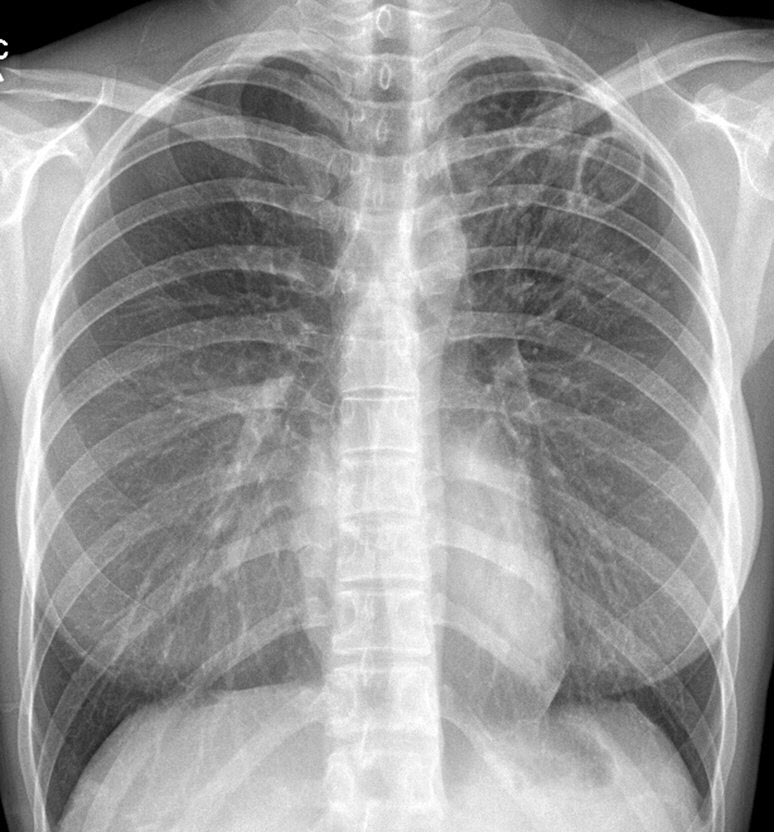

결핵 진단은 흉부 엑스선 검사, 객담 도말 검사, 객담 배양 검사로 객담에서 결핵균을 체크하는 방법으로 진행해요. 취침 시에 기관지 속에 결핵균이 고여서 증식하여서 기상한 뒤에 깊게 기침을 하여 아침의 첫 가래를 뱉은 후 검사를 진행해요. 가래는 3일간 매일 한번 아침에 기상한 직후의 객담을 모은 것으로 검사해요.

요즘 활발히 계획한 대로 일을 되는 검사법은 결핵 유전자를 이용한 진단법으로, 기존의 배양법보다 더 많이 정확한 방법이라고 합니다. 그리고 혈액 속의 백혈구가 생산하는 인터페론 감마의 수치를 도량해서 결핵을 진단하는 방법도 존재하지만 이는 결핵균에 노출이 된 실태를 증명할 뿐이며 활동성 결핵 가부를 알 수 없다고 한다는 단점이 있고요.